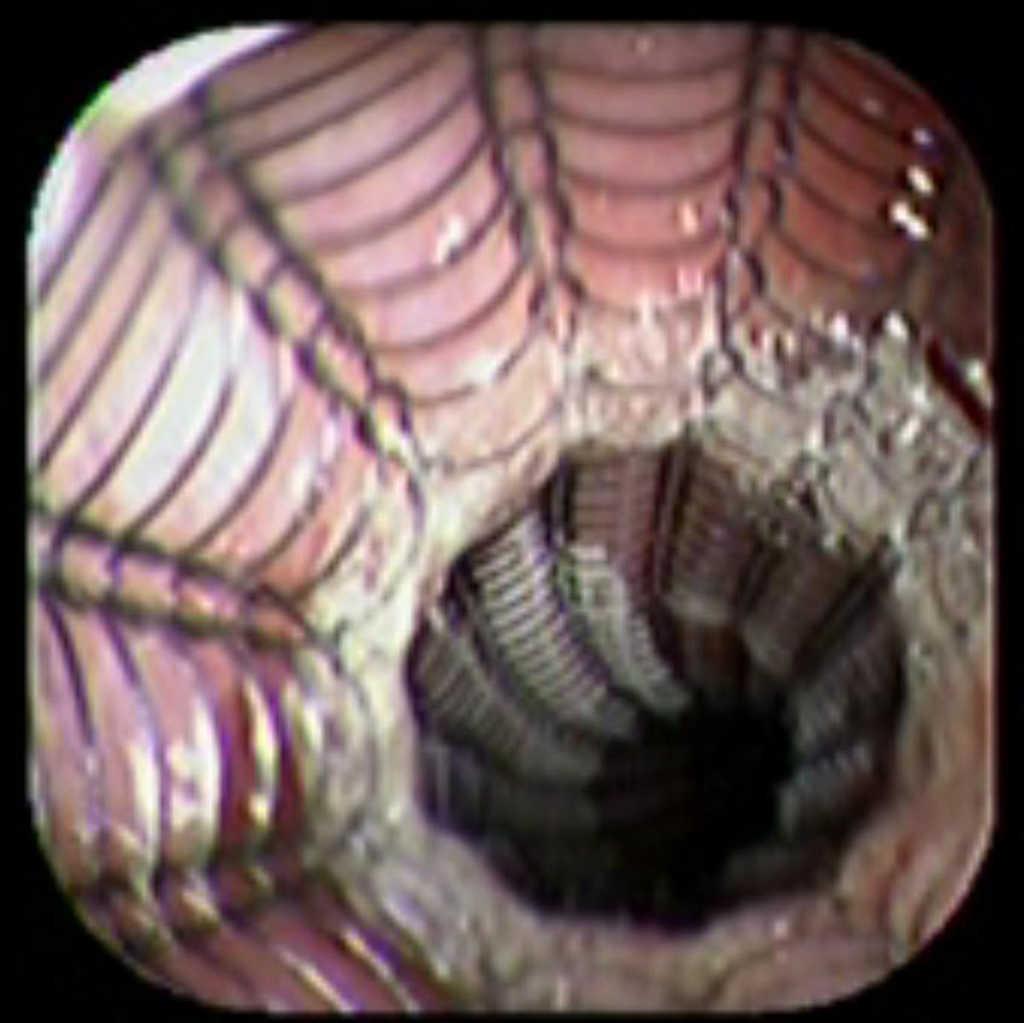

Case reportA 41-year-old man underwent elective laparoscopic Heller myotomy for achalasia; during the procedure a perforation of the esophageal wall was observed, and primary closure of the defect was attempted. The patient started with PO on day three, but he complained of chest pain and fever. Immediately CT scan with oral contrast was performed. A free leakage at esophago-gastric junction was observed. A 15 cm PSEMS (Ultraflex esophageal NG covered (120 mm) stent, Boston Scientific, Natick, MA) was placed across the defect, leading to the distal 1.5 cm non cover into the stomach and the proximal 1.5 cm non cover at 30 cm from incisor (Figure 1). A control CT scan with oral contrast showed good position of the stent, without evidence of leakage. The patient's clinical status improved and began to swallow normally, but showed numerous episodes of reflux despite PPI use. We leave the PSEMS for 26 days beside the reflux symptoms. During the endoscopic procedure to remove the stent the presence of tissue embedding along the covered portion of the PSEMS was noted (Figure 2). The stent was pulled out with an alligator forceps with out major complications and the cover of the PSEMS was seen to be totally destroyed (Figure 3).

Figure 1. The image shows the stent application.